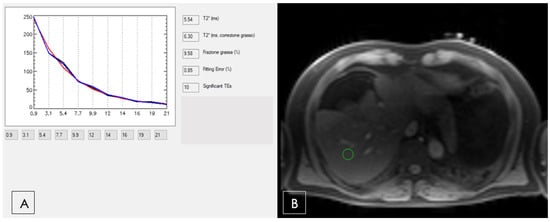

- Positano, V.; Salani, B.; Pepe, A.; Santarelli, M.F.; De Marchi, D.; Ramazzotti, A.; Favilli, B.; Cracolici, E.; Midiri, M.; Cianciulli, P.; et al. Improved T2* assessment in liver iron overload by magnetic resonance imaging. Magn. Reson. Imaging 2009, 27, 188–197. [Google Scholar] [CrossRef]

- Meloni, A.; Positano, V.; Keilberg, P.; De Marchi, D.; Pepe, P.; Zuccarelli, A.; Campisi, S.; Romeo, M.A.; Casini, T.; Bitti, P.P.; et al. Feasibility, reproducibility, and reliability for the T*2 iron evaluation at 3 T in comparison with 1.5 T. Magn. Reson. Med. 2012, 68, 543–551. [Google Scholar] [CrossRef]

- Reeder, S.B.; Yokoo, T.; França, M.; Hernando, D.; Alberich-Bayarri, Á.; Alústiza, J.M.; Gandon, Y.; Henninger, B.; Hillenbrand, C.; Jhaveri, K.; et al. Quantification of Liver Iron Overload with MRI: Review and Guidelines from the ESGAR and SAR. Radiology 2023, 307, e221856. [Google Scholar] [CrossRef]

- Positano, V.; Meloni, A.; Santarelli, M.F.; Pistoia, L.; Spasiano, A.; Cuccia, L.; Casini, T.; Gamberini, M.R.; Allò, M.; Bitti, P.P.; et al. Deep Learning Staging of Liver Iron Content From Multiecho MR Images. J. Magn. Reson. Imaging 2023, 57, 472–484. [Google Scholar] [CrossRef]